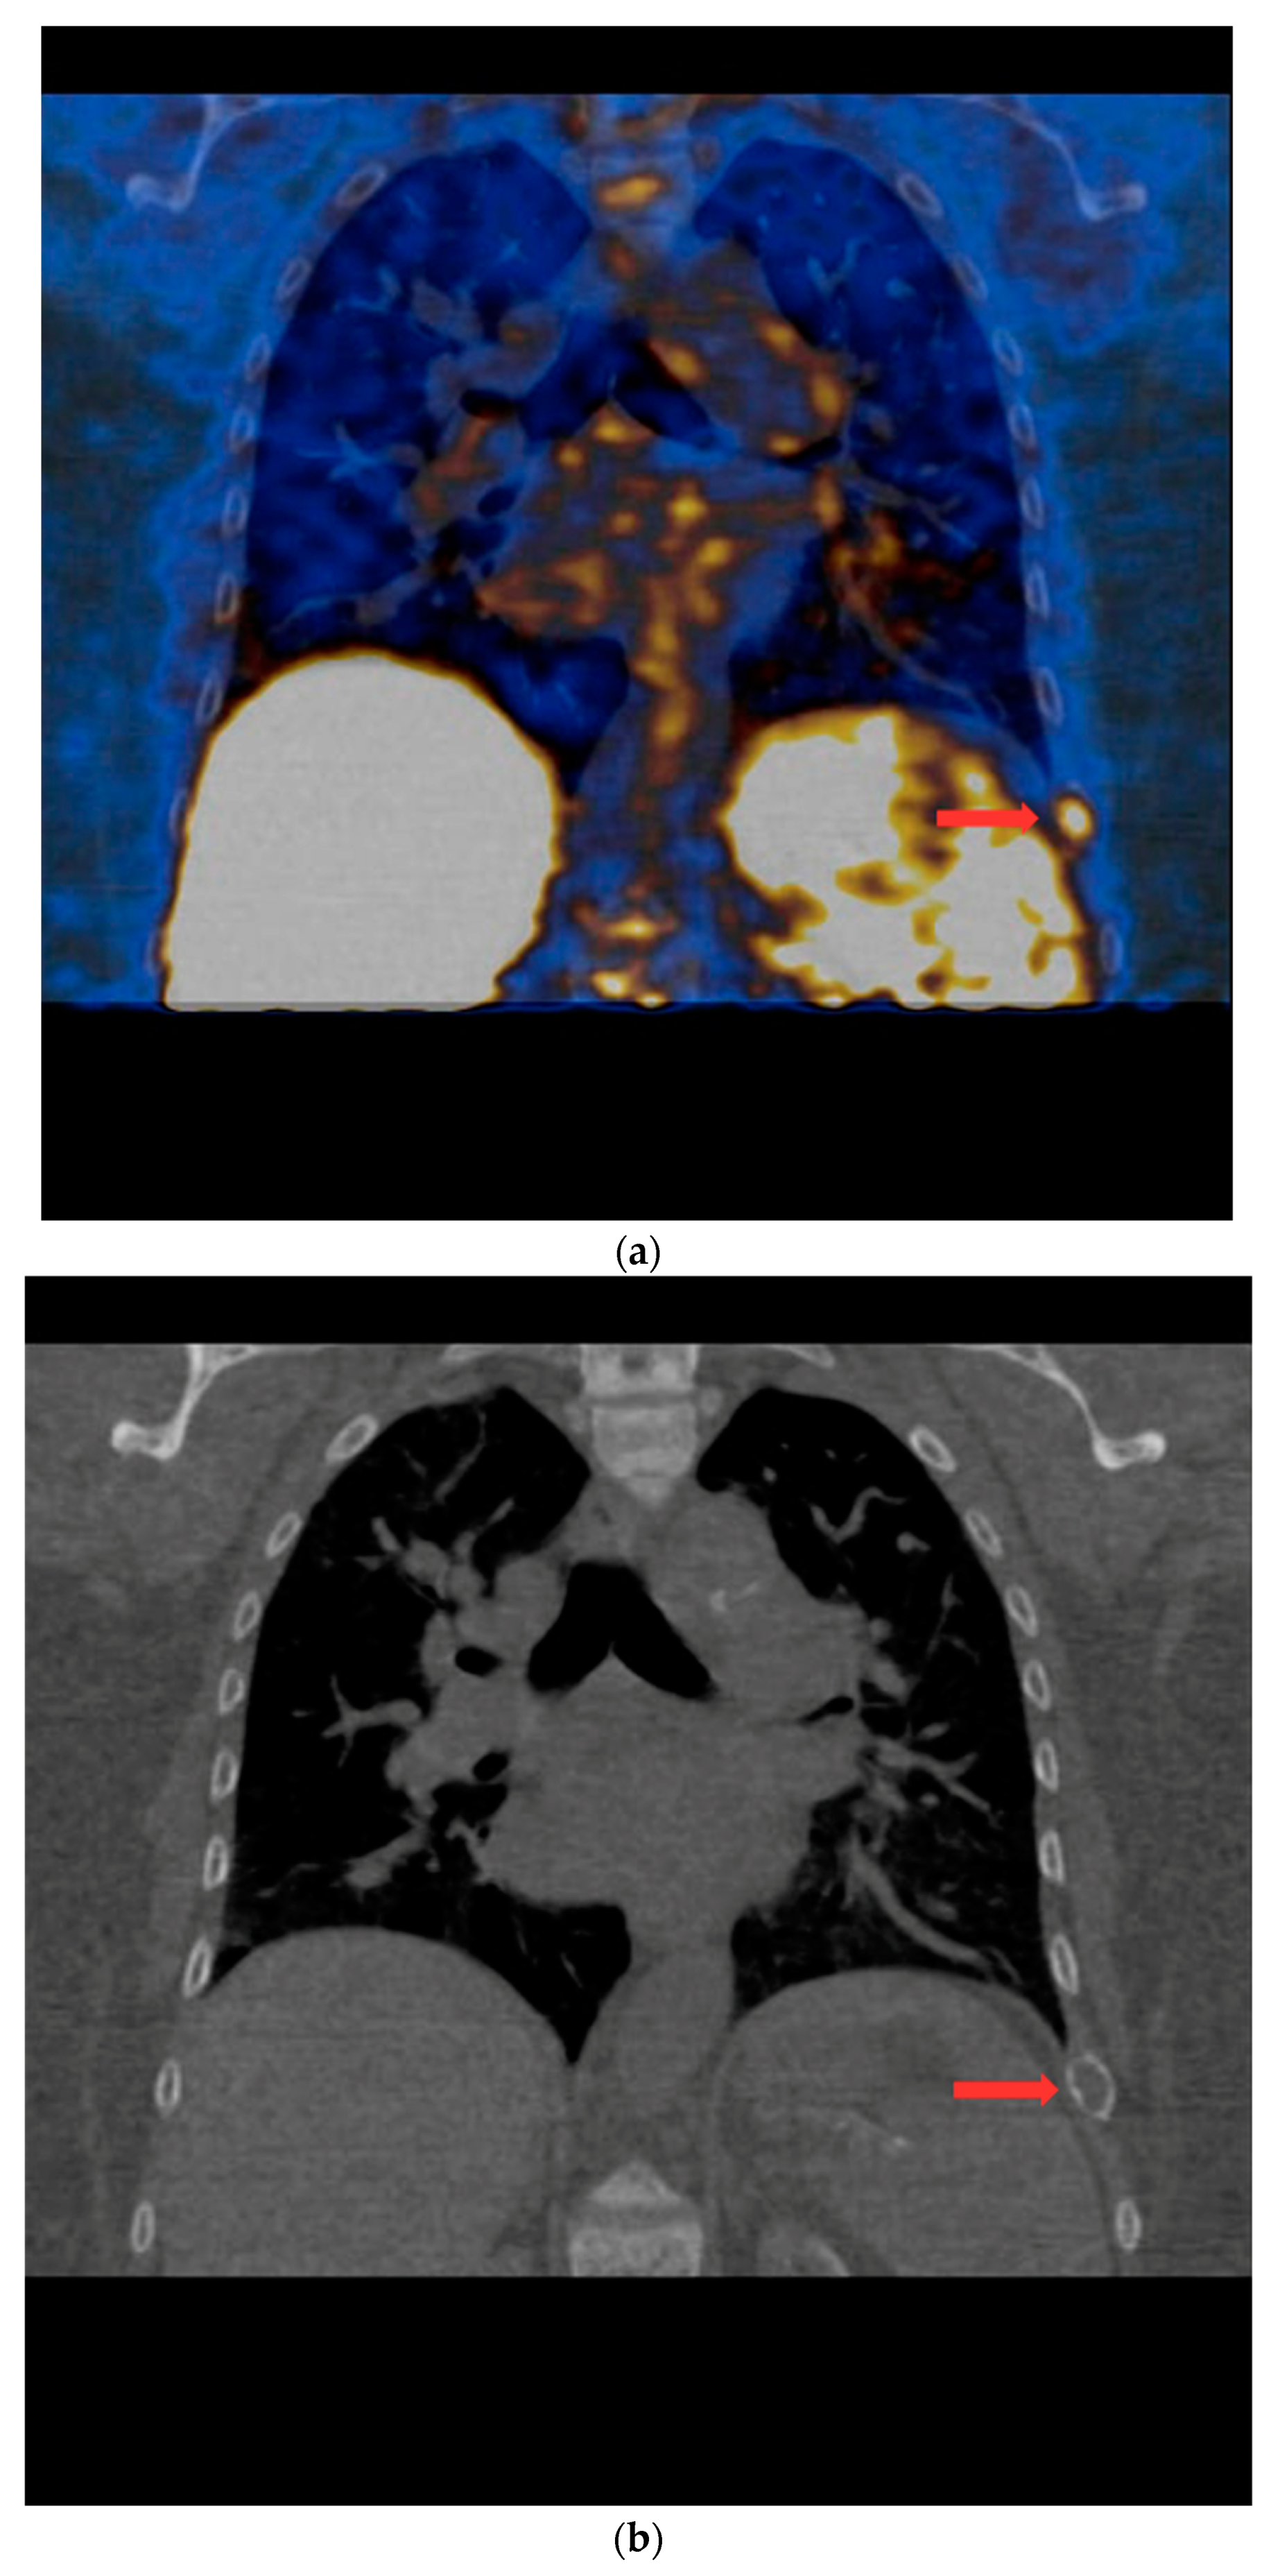

PET/CT with [11C]MET was performed on 19 patients, with negative results for both first-line imaging examinations. In this group, a positive result was obtained in 89.5% of the patients (17/19) (Figure 1 and Figure 2). In 2 patients (10.5%), the result was assessed as inconclusive (both of these patients showed accumulation of the radiotracer in a single lesion, the location and structure of which indicated that it might be a mediastinal lymph node; however, these lesions were not histologically verified due to revealed contraindications for surgery). Multiple lesions were observed in 57.9% of the patients (11/19) (Figure 3). Ectopic lesions were observed in 21.1% of the patients (4/19) (Figure 4). In total, 34 foci of increased accumulation of the radiotracer, considered as parathyroid glands, were observed. Additionally, in 15.8% of the patients (3/19), foci of increased accumulation of the radiotracer in the bones corresponding to brown tumors were observed (Figure 5a,b). Detailed results of the PET/CT examinations with [11C]MET are shown in Table 1.

Figure 5.

(a) PET/CT with [11C] MET—frontal projection. Visible focal increased radiotracer uptake (red arrow) corresponding to the brown tumor in the middle part of the left 9th rib. (b) Low-dose CT scan performed during PET/CT with [11C]MET in the same patient. In the location of the focus of increased accumulation of the radiotracer corresponding to the brown tumor of the left 9th rib, the distention of the contour of this rib is visible (red arrow).